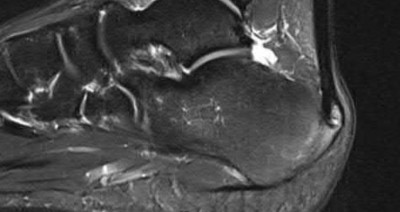

A 38-year-old male suffers the injury shown in Figure A. During operative fixation, free osteoarticular fragments are encountered and reconstruction of these pieces is attempted. Postoperatively, which of the following will have the most beneficial effect on the healing potential of the surviving chondrocytes within these reconstructed articular segments?

Figure A demonstrates a comminuted tibial plateau fracture with significant intra-articular involvement. Basic science evidence has demonstrated that post-operative gentle compressive loading may have a positive impact on articular cartilage healing; however, excessive shear loading may be detrimental.

Irrgang et al provide guidelines for rehabilitation following surgical management of articular cartilage lesions of the knee. They state that after articular cartilage repair, exercises to enhance muscle function must be done in a manner which minimizes shear loading of the joint surfaces in the area of the lesion. The authors also discuss the benefits of gentle compressive loading and motion of the joint, and its positive effects on chondrocyte nutrition.

Furthermore, they recommend a period of protected weight bearing as often being necessary, and that this should be followed by progressive loading of the joint.